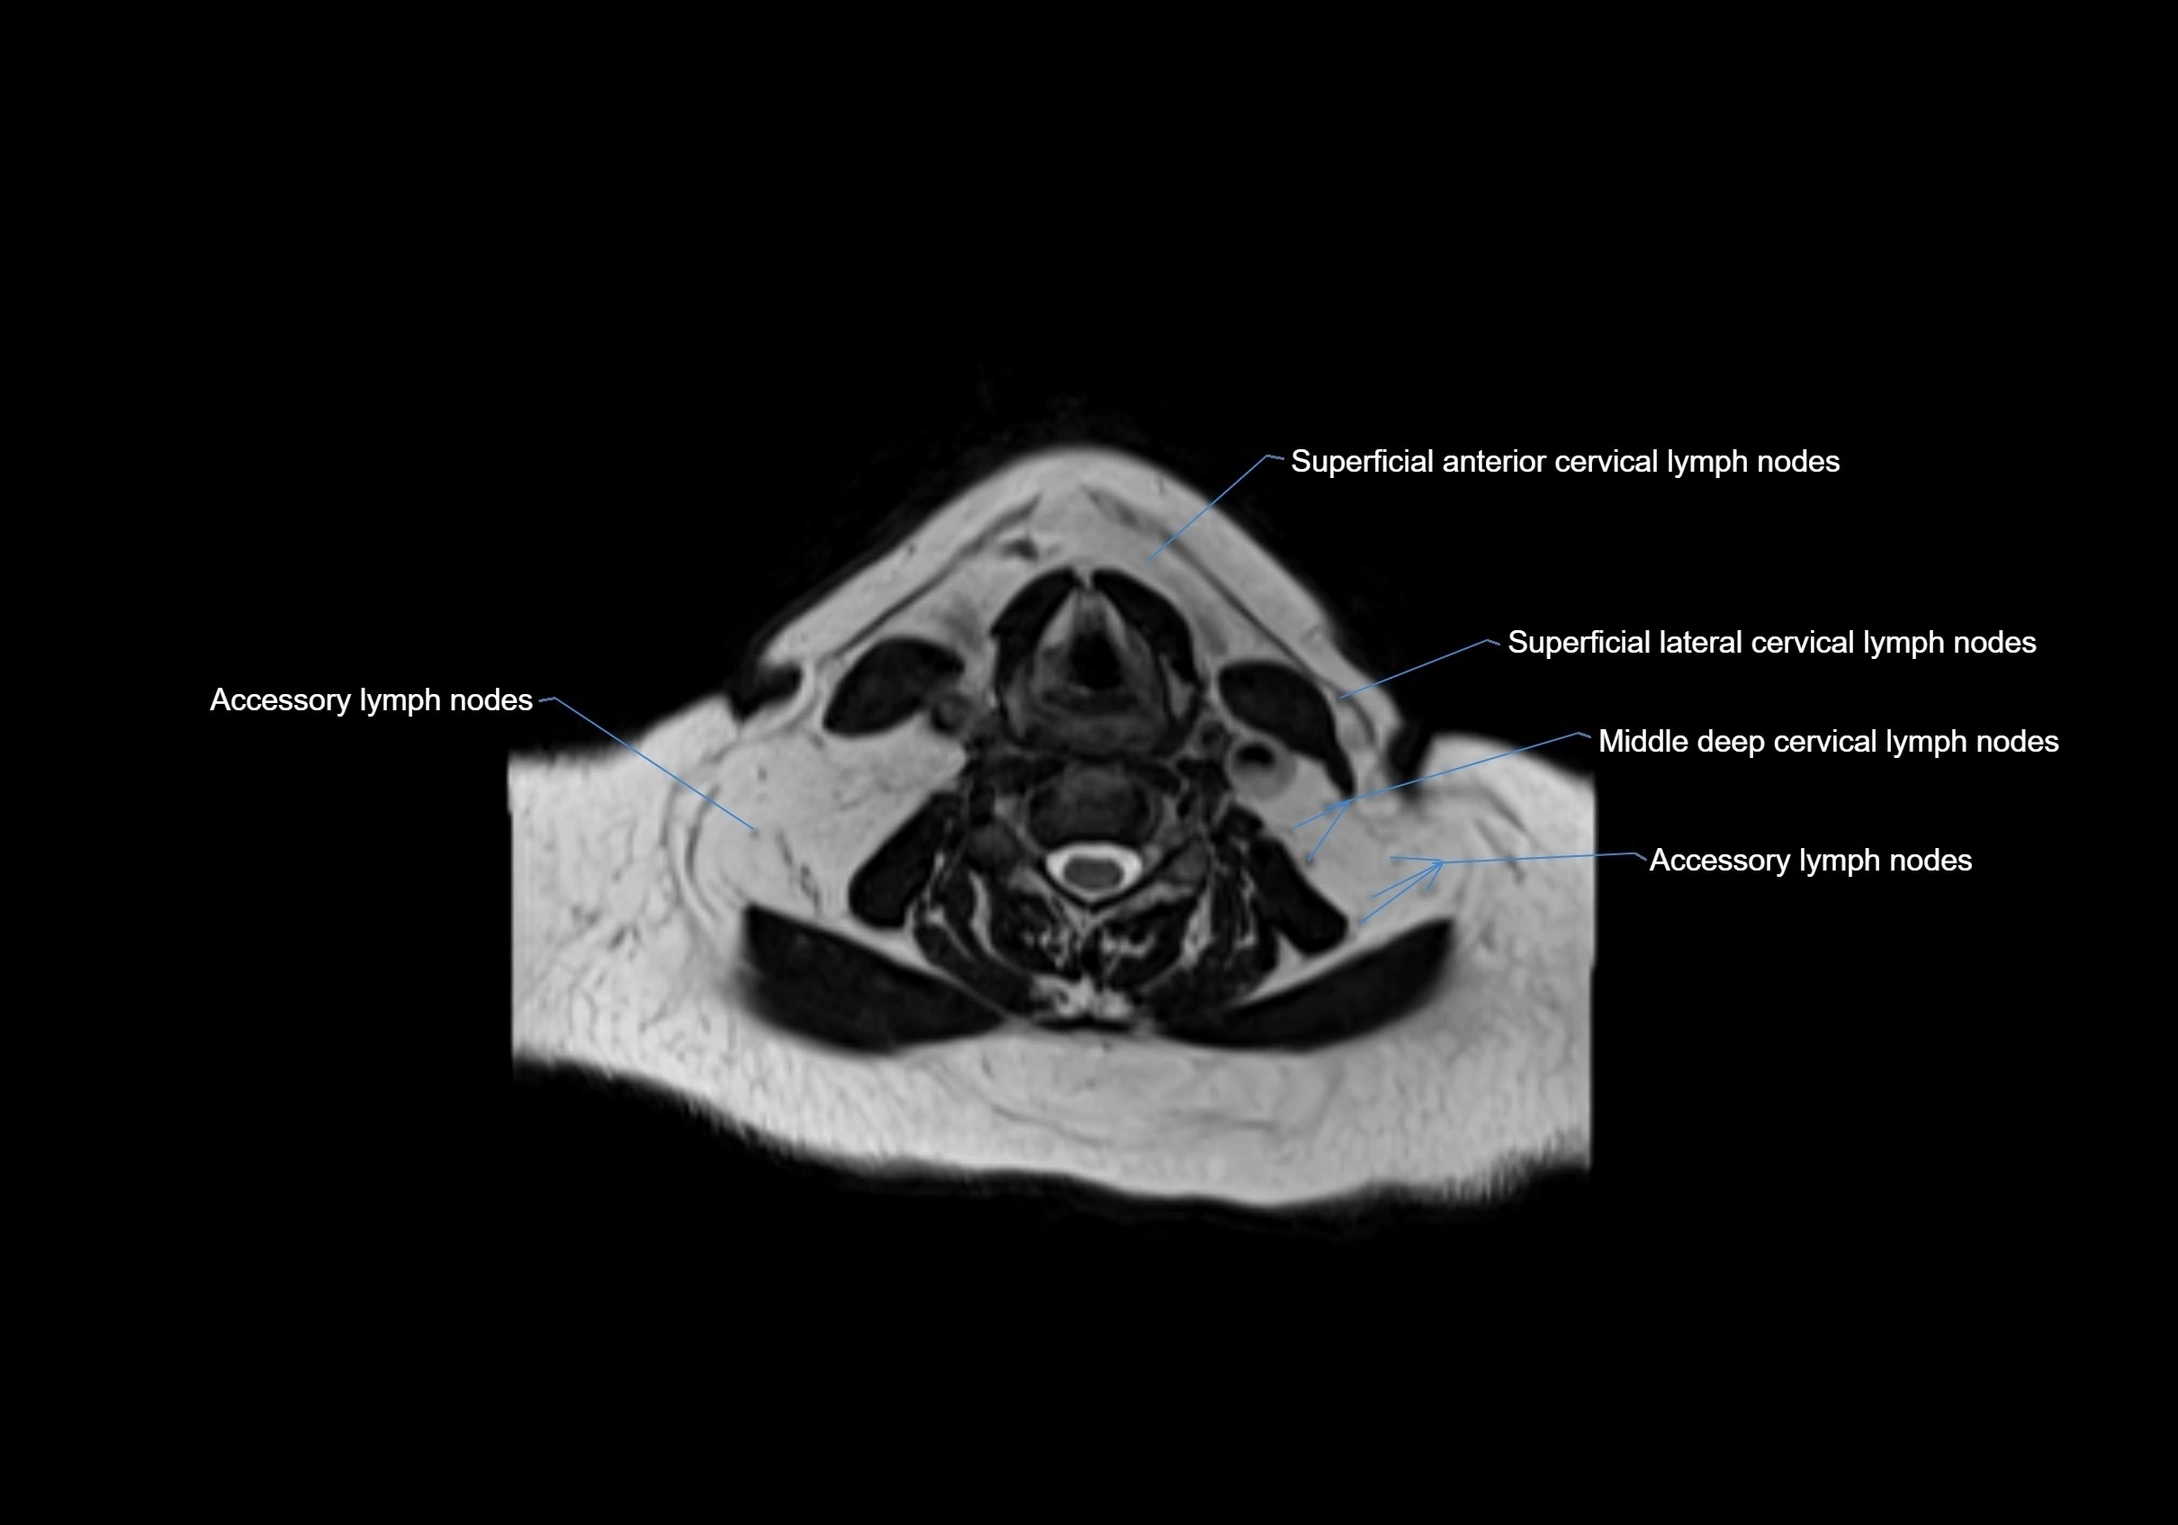

Accessory lymph nodes

Accessory lymph nodes are small, secondary lymph nodes located along the main facial and cervical lymphatic chains, often adjacent to primary lymph nodes, such as preauricular, submandibular, or occipital nodes. They are typically less than 5 mm in diameter, embedded within subcutaneous fat or connective tissue, and may be variable in number and location. These nodes provide additional filtration and immune surveillance for lymph collected from the face, scalp, and neck regions. Accessory lymph nodes are usually non-palpable in healthy individuals but may enlarge in response to infection, inflammation, or metastasis, making them clinically significant.

Location

• Found along primary lymph node chains, including preauricular, submandibular, parotid, and occipital regions

• Embedded in subcutaneous fat or superficial fascia, often lateral or posterior to primary nodes

• Variable in number; may occur unilaterally or bilaterally, depending on individual anatomy

MRI images

image